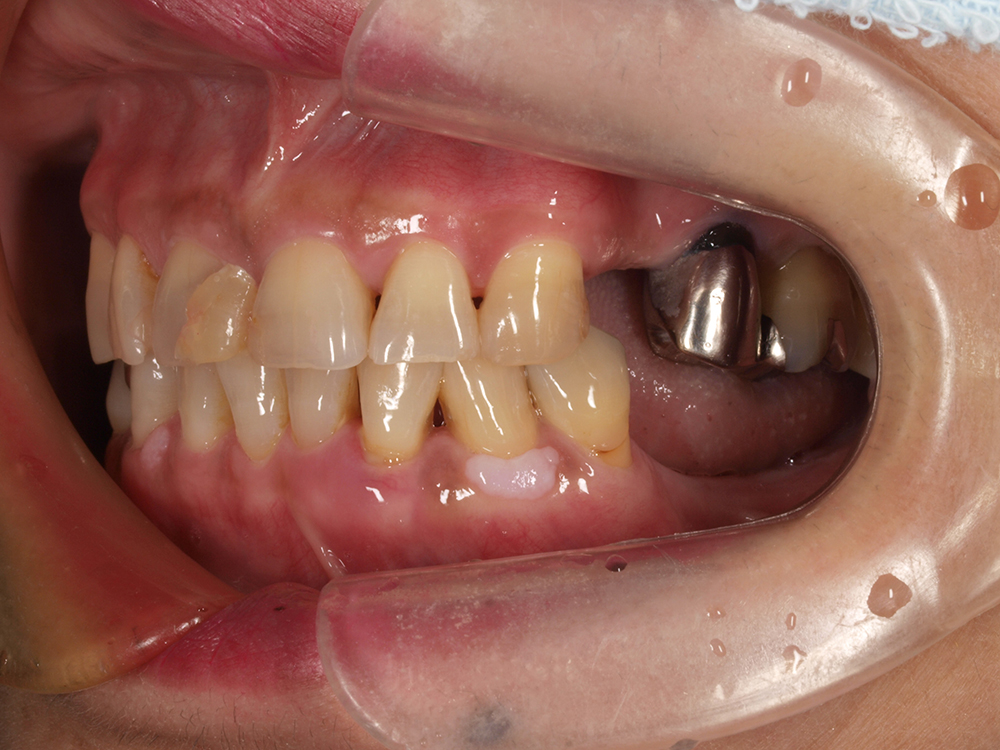

55歳 男性

- 主訴

- 前歯でしか咬めなく、食事を採るのに非常に困難で辛い

- 処置内容

- 上顎6本、下顎3本

- 治療費用

- 上顎:約230万(税込)下顎:約120万(税込)

- 治療期間

- 上顎:1年(仮歯まで8か月)下顎:8か月(仮歯まで5か月)

- リスク

- 上部構造物、仮歯の破折、術後の腫れ(3日)、人工歯根脱落リスクがあります